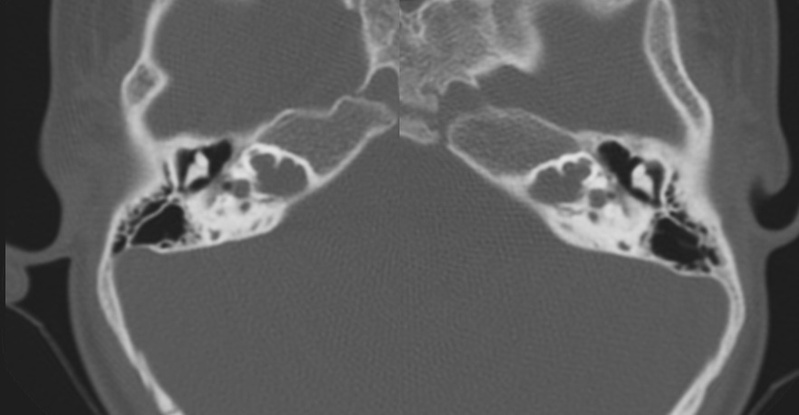

El estudio de imagen se realizó mediante TC de oídos y mastoides. Se aplicaron en cuatro pacientes varones y una madre oyente considerada portadora. Los estudios se clasificaron según Sennanoğlu y cols. [8,9,13].

Evaluación de Imagen (TC)

Los hallazgos radiológicos, mediante TC de oídos a cuatro pacientes varones y una madre oyente, portadora obligada, se analizaron y clasificaron según Sennanoğlu et al. [8,9]. En ese sentido, son consistentes con PI-III en tres de ellos: IV-1, IV -2 y IV- 4. El paciente IV-3 mostró PI-I; la madre portadora obligada no mostró alteración alguna (Ver Tabla 3). En los cuatro pacientes estudiados de esta familia observamos dos tipos de MOI, PI-I y PI-III, incluso entre los hermanos IV-2 y IV-3, que presentaron diferente tipo de PI, lo que evidencia expresividad variable. La malformación PI-III es de las MOI menos frecuente y se encuentra presente en este estudio familiar como predominante.

El estudio con TC de una de las madres portadora no mostró MOI, por lo que supondríamos, que al menos en su caso, no existe expresividad menor del gen involucrado. Como se trata de una sola mujer portadora, no podemos asegurarlo, pero es probable que las portadoras no presenten manifestaciones menores, al menos en algunos casos. Es necesario, además del seguimiento audiológico, extender el estudio de imagen al resto de las portadoras.